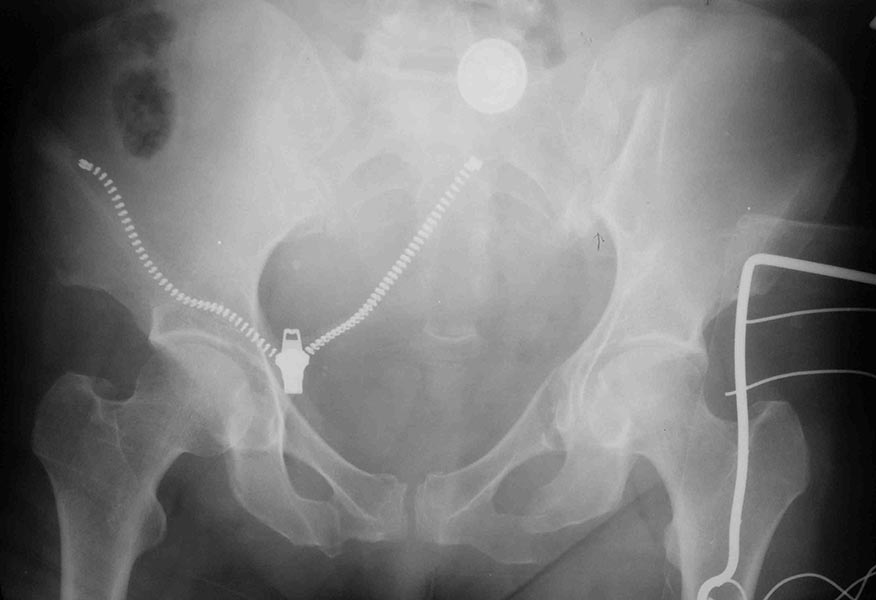

Re: Вертикально нестабильный таз

Похожий таз прооперировали сегодня, правда сзади - открыто, удалось провести IS винт (но места было очень мало. Человеческие проекции постараюсь выслать в ближайшее время.